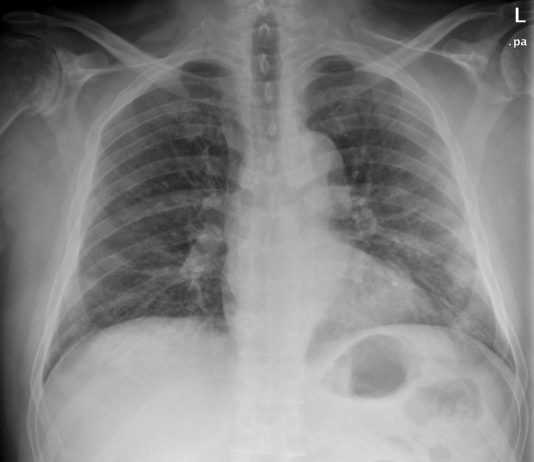

47-year-old male

patient with asthenia, arthralgia, headache, sick cough and fever 39°C since

March 1 presented to the ED on...